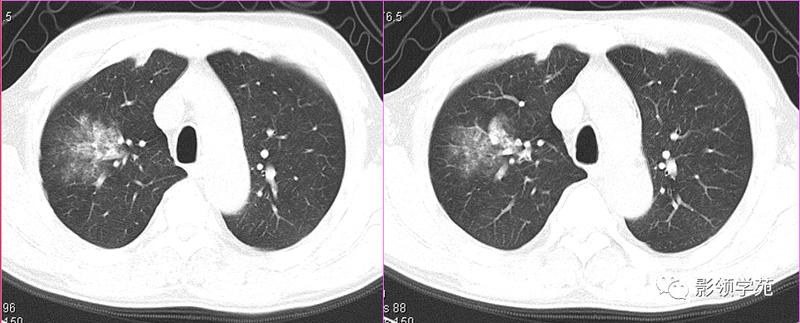

肺结核的渗出性改变:片状、边界模糊

有硬化部分的磨玻璃样变

过敏性肺炎

马赛克征

肺出血(片状、边缘模糊)